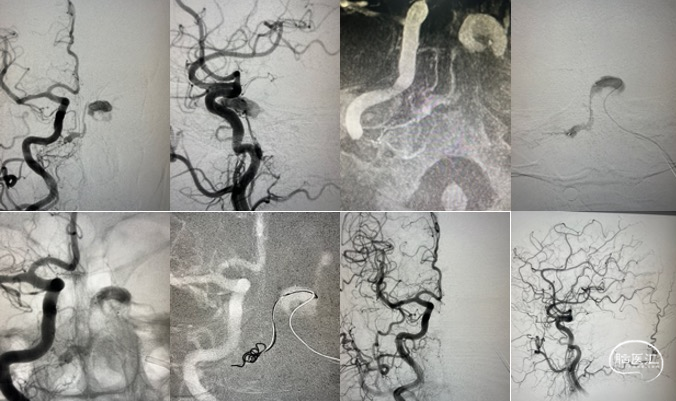

患者入院2月前无明显诱因下出现左侧耳鸣,呈吹风样,持续性,节律与脉搏一致,无明显加重缓解因素,声音与头位或体位无关,无头痛头晕,无恶心呕吐,当时就诊当地医院对症处理,无好转。入院1天前就诊于当地医院查MRA(图1)及脑血管造影(图2)提示“左侧颈外动脉造影见咽升动脉供血通过岩上窦、海绵间窦向双侧颈内动脉引流的动静脉瘘。左侧椎动脉造影显示左侧椎动脉开口无狭窄,椎动脉硬膜支供血向同侧椎旁静脉引流的瘘形成”,现为进一步治疗来院。

根据病史及当地医院辅助检查,诊断后颅窝硬脑膜动静脉瘘明确。分析当地医院MRA及血管造影结果,大致可判断该患者瘘口位于左侧舌下神经管或髁前汇区。详细读片可见左侧颈外动脉造影及椎动脉造影所示引流模式相同。入院后完善脑血管造影检查,并应用双容积影像后处理技术进行三维重建(图3)。便于进一步分析血管构筑,制定手术策略。

根据患者术前血管造影表现,该例病例确诊为左侧舌下神经管区硬脑膜动静脉瘘。分析其血管构筑特点:供血动脉为颈外动脉咽升动脉分支,椎动脉脑膜支,瘘口位于左侧舌下神经管区,经岩下窦向同侧海绵窦-海绵间窦-对侧海绵窦引流,并经髁前静脉向椎旁及椎管内静脉引流。患者有显著的搏动性耳鸣症状,且引流静脉具有出血风险,手术指征存在。笔者所在的中心既往诊疗的病例表明,舌下神经管的引流模式多种多样,但多数可见髁前静脉向岩下窦汇合。该患者亦有此静脉引流通道(图3黄色箭头所示),因此介入栓塞的路径上可考虑经要岩下窦-髁静脉路径。

术中将导引导管置于左侧颈内静脉,并引导至左侧岩下窦,Echelon-10微导管经由髁静脉超选至瘘口处。微导管到位后再次进行双容积三维后处理,验证微导管到位位置为术前所判断的瘘口处(图4),随后在瘘口放置一枚弹簧圈,并在阴性路图下注入Onyx胶0.8ml(图5)。复查造影见瘘口完全栓塞,异常引流彻底消除(图6)。

栓塞术后即刻CT未见颅内出血或Onyx胶异位栓塞。麻醉复苏后患者诉耳鸣消失,未诉其他不适,查体无新发神经系统体征。术后第二日,复查CT未见异常(图7),患者顺利出院。

患者术后半年于当地医院复查血管造影,提示瘘口完全栓塞,未见复发(图8)。

图8. 术后半年复查脑血管造影。